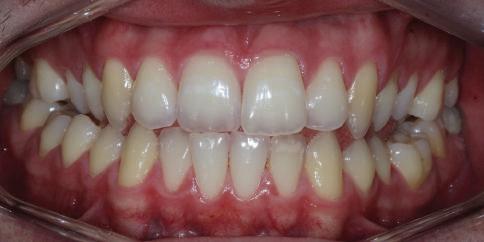

Dental Tribune Bulgarian Edition / октомври 2022 г.16 клиничен случай с алайнери Г орният латерален ре зец е вторият найчесто вродено липсващ зъб.1,2 Поради разполо жението му във видимата зона на усмивката лечение то на подобни случаи нала га мултидисциплинарен под ход, целящ отличен функцио нален и естетичен резултат. Налице са няколко лечебни мо далности, свързани с различ но разпределение на място то: първият вариант е орто донтско отваряне на място и възстановяване на липсва щия зъб с конструкция, под държана от съседните зъби3 или от имплант4, докато при втория подход разстоянията се затварят и премоларът заема мястото на канина.5 Изборът на лечебен подход трябва да бъде направен съв местно от зъболекар и паци ент въз основа на очакванията на последния и предвиди мостта на лечението. Множе ство фактори влияят върху това решение, като напри мер типа малоклузия, размера, формата и цвета на кучеш ките зъби6, оклузалните вза имоотношения (овърджет и овърбайт), лицевия профил, дължината на зъбната дъга и несъответствията в разме ра на зъбите.7 В настоящата публикация се разглежда случаят на жена в зряла възраст с вродена лип са на горен ляв латерален резец. Бяха приложени про зрачни алайнери за отваряне на място за единичен им плант и бяха постигна ти функционална оклузия и отлична естетика. ПРЕДСТАВЯНЕ НА СЛУЧАЯ Диагноза Пациентката бе на 32 годи ни, когато лечението започна, и първоначалното ѝ състоя ние бе следното (фиг. 1–3): липсващ горен ляв латерален резец; клас II, подклас I малоклузия; отклонение на горната сре динна линия вляво; Доклад на клиничен случай ЛЕЧЕНИЕ С АЛАЙНЕРИ НА ПАЦИЕНТ С АГЕНЕЗИЯ НА ЛАТЕРАЛЕН РЕЗЕЦ Д-р Iro Eleftheriadi и д-р Christodoulos Laspos, Гърция и Кипър Фиг. 1a–h Предоперативни лицеви и интраорални снимки. Фиг. 2a–e Дигитални модели преди началото на лечението. Фиг. 3 Панорамна снимка преди лечението. Фиг. 1a Фиг. 1d Фиг. 1f Фиг. 2a Фиг. 2d Фиг. 2b Фиг. 2e Фиг. 3 Фиг. 2c Фиг. 1b Фиг. 1e Фиг. 1g Фиг. 1h Фиг. 1c

Dental Tribune Bulgarian Edition / октомври 2022 г. 17клиничен случай с алайнери леко струпване в долната че люст; несъответствие по Болтън (мандибуларен излишък от 3.06 мм във фронталната зона и общо 1.47 мм); издължено лице с лицева аси метрия; конвексен профил с ретруди рана долна челюст и проми нентен нос. На мястото на зъб #46 бе на лице имплант, а зъби #16 и 26 са ендодонтски лекувани. Тези зъби бяха асимптоматич ни, затова бе взето решение да се прави релечение само при нужда. Мъдреците липсваха. Анализът на телерентгеногра фията (фиг. 4) показа ретрог натна мандибула (SNB: 74.2°) и нормална инклинация на резците както в

Цели на лечението и лечебен план Целите на лечението бяха следните: нивелиране и подреждане на зъбите и в двете зъбни дъги; отваряне на пространство за липсващия латерален резец; коригиране на отношенията при канините и моларите до клас I; и корекция на отклонението на срединната линия. Лечебният план включваше: корекция на отношенията при кучешките зъби и мола рите до клас I с дистализира не на максилата; отваряне на пространство в областта на #22 за поставя не на единичен имплант; корекция на срединната ли ния; и създаване на място за раз ширяване на зъб #12 и апрок симална редукция в долната челюст с цел подобряване на несъответствието по Болтън и осигуряване на подобра оклузия. Изпълнение на лечебния план Този случай бе изпълнен със системата за алайнери Invisalign (Align Technology). Одобреният първоначален лечебен план предвиждаше 49 алайне ра с дистализиране на задни те горни зъби до клас I (прибли зително с около 3.5 мм; фиг. 5). За бъдещия имплант в областта на липсващия латерал бе планирано пространство от 6.5 мм, докато във фронталния сегмент на долната челюст бе предвидена апроксимална редук ция. В дясната страна бутон за ластици клас II бе поставен на зъб #47 вместо на зъб #46, за да не се увреди короната на импланта. Понеже пациентката жи вееше в чужбина,

планта бе поставена временна коронка (фиг. 10 и 11), докато бъде изготвена окончателна та. Бе постигнат отличен кра ен резултат. Меките тъка ни около импланта напълно заздравяха, което доприне се за перфектната хармония между бяла и розова естетика (фиг. 12–15).

Dental Tribune Bulgarian Edition / октомври 2022 г.18 воначалния план. Тези пробле ми бяха адресирани чрез допъл нителна поръчка на алайнери с торк контрол и зададено екст рудиране на задните зъби с цел установяване на добри оклузал ни контакти в дисталните об ласти, като бяха предвидени и оптимизирани атачмънти с контрол над корените за корекция на ангулацията на макси ларните резци (фиг. 8). Резултати от лечението Панорамната рентгено графия след ортодонтското лечение показа благоприятна паралелна позиция на съседни те зъби, подходяща за поставя не на имплант в областта на #22, както и конвергенция на ко рените на зъби #44 и 45 (фиг. 9), но преценихме, че няма да от деляме допълнително лечебно време за коригирането ѝ поради факта, че пациентката бе мно го доволна от постигнатия до момента резултат. След при ключване на лечението бяха постигнати отлични взаимо отношения клас I при мола рите и канините, а срединни

съвпадаха. Върху им

(LFH: 56.5 mm) и размерите на меките тъка ни останаха непроменени. На клонът на горните резци бе за пазен (Ui–FH: 115.8°), а долните резци бяха леко наклонени ве стибуларно (Li–APog: 30°; фиг. 16). ДИСКУСИЯ Липсата на зародиш на по стоянен горен латерален резец е налице при 3.5–6.5% от евро пеидната раса, като при жени е по-честа, отколкото при мъ жете в съотношение 3:2.8–10 Възможни са няколко лечебни подхода, включително замя ната му с преоформен канин, отваряне на място чрез орто донтско лечение и протетич но възстановяване, както и ав тотрансплантация. Устано вено е, че изборът за затваря не на място или за отваряне то му все още подлежи на дис кусия сред ортодонти и проте зисти.11,12 Според литературните дан ни затварянето на простран ството и замяната на липсва щия латерал с канин се предпо чита в случаи на едностранна липса на зародиш, балансиран профил, кучешки зъби и премола ри със сходна форма и цвят, дву челюстна протрузия или клас II малоклузия.13–15 Отваряне на пространство по-често се изби ра при клас I, наличие на диасте ми и треми в горната зъбна дъга или голяма разлика в размерите на канини и премолари.16 Скорошно проучване е уста новило, че изборът на лечение при конгенитално липсващ ла терал е пряко свързан със след ните фактори17: възрастта на пациента при започване на лечението; индивидуалните особености при всеки конкретен случай; и сътрудничеството между специалистите в лекуващия екип. Макар да има проучвания, фа воритизиращи леченията със затваряне на място11,18, всеки случай трябва да бъде оценяван индивидуално. В презентирания в тази статия случай бе взето решение за отваряне на мяс то и протетично възстановя ване, понеже целта бе да се по стигнат клас I отношения при канините и моларите, както и по-широка усмивка. За да се из бегнат компромиси, след лече нието бе постигнат клас I при моларите и кучешките зъби, несъответствието по Болтън бе подобрено и срединната ли ния бе коригирана. Други изслед вания демонстрират отлични естетични и функционални ре зултати при лечение с отваря не на място и протетична ре хабилитация.19 И двете лечеб ни модалности са подходящи за третиране на вродена лип са на зародиш на латерал и да ват сходни функционални и па родонтални резултати20, като при едно проучване